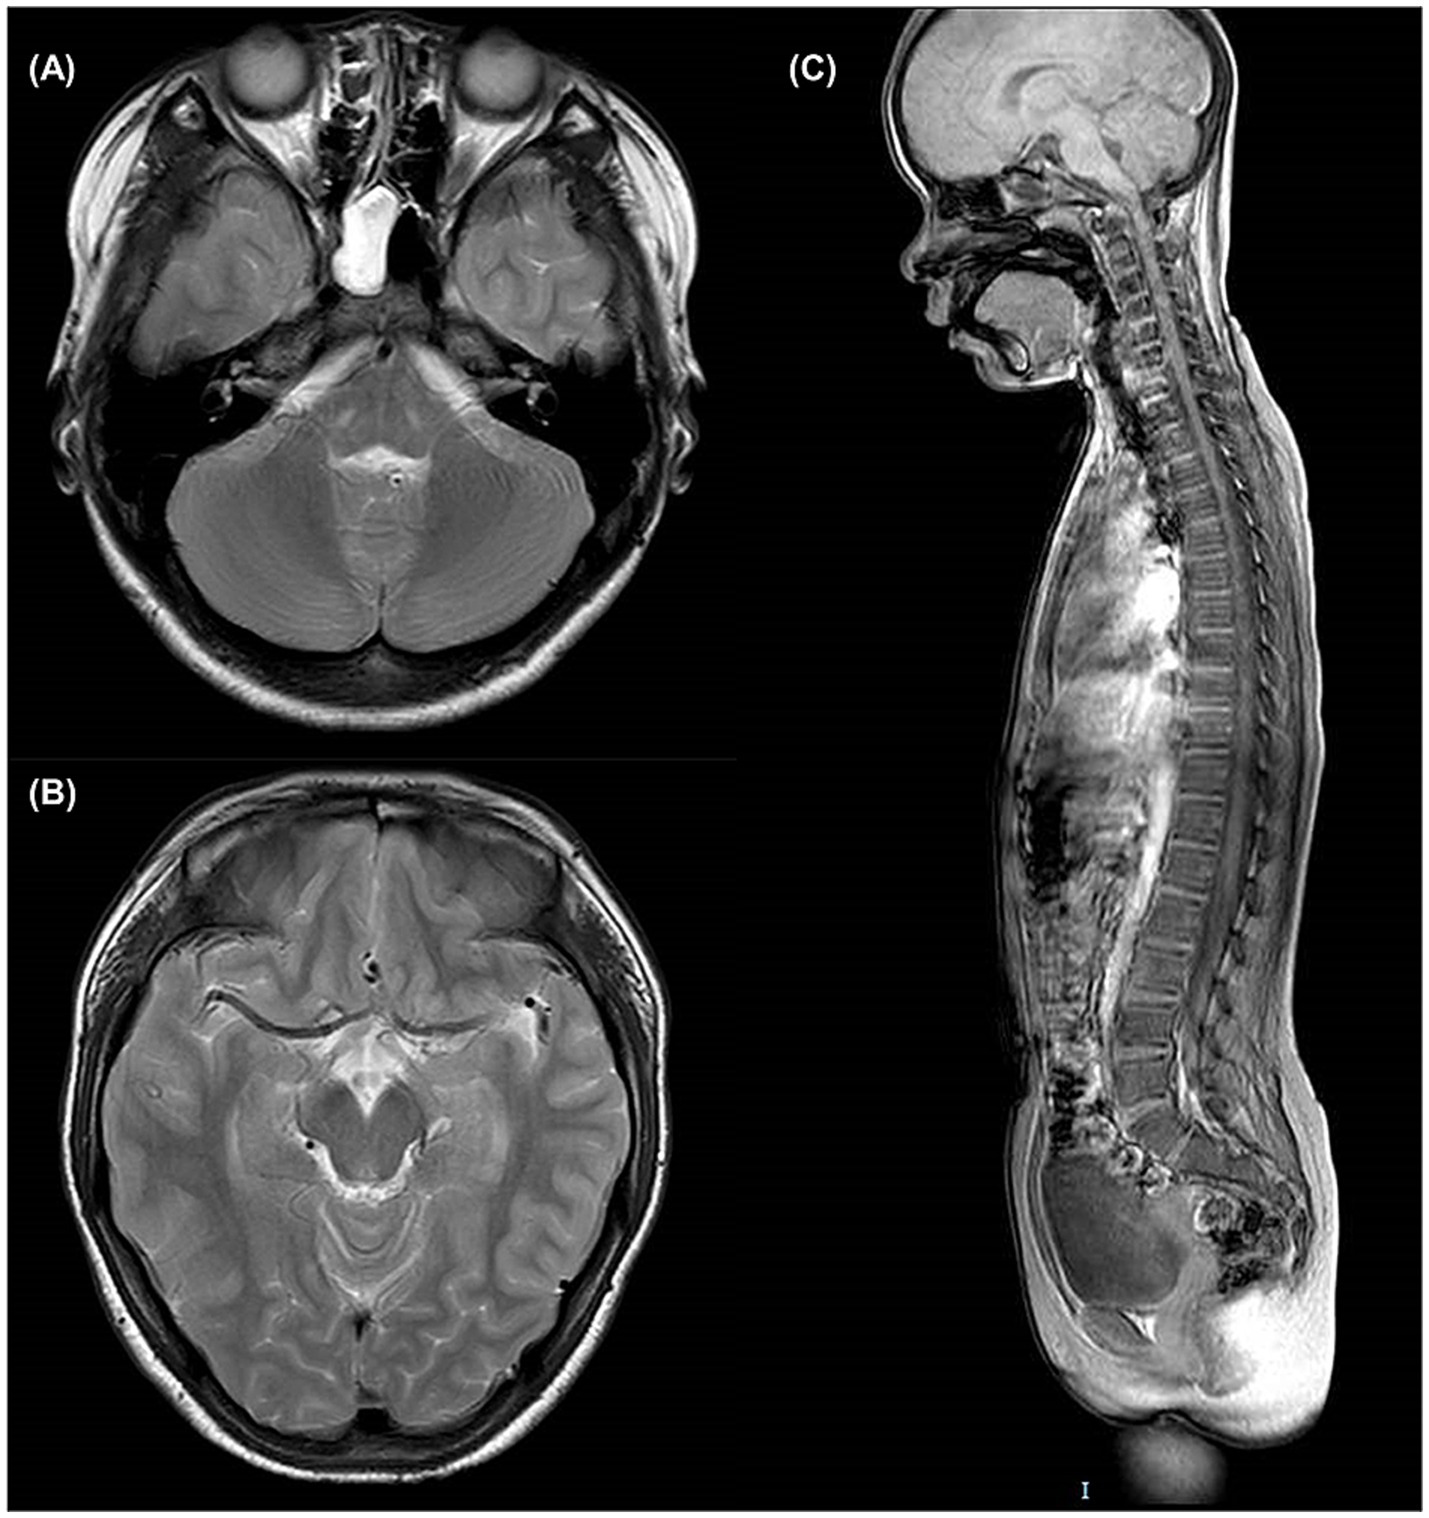

3.3 Imaging investigations

No obvious lesions were observed in the brain and spinal MRI of patient III2 (Figure 2), particularly at the level of the mesencephalon and pons, where the “fork and bracket” signs were previously reported in Syrian (16) and Bedouin (9) families.

Figure 2

Brain and spinal MRI of patient III2. (A) T2-weighted axial slice at the level of pons. (B) T2-weighted axial slice at the level of mesencephalon. (C) T1-weighted sagittal slice of the entire spine.